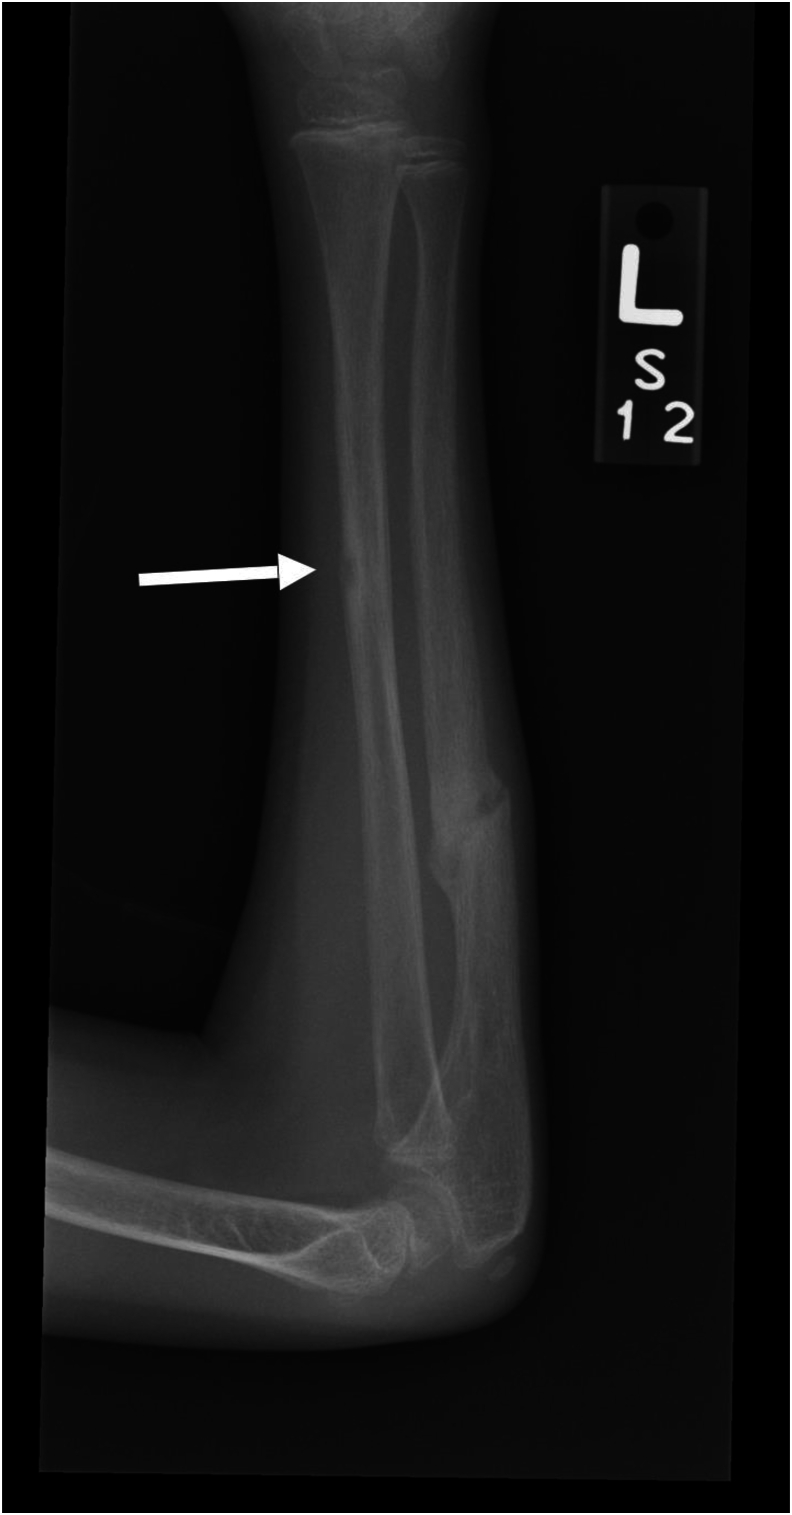

Background: Osteogenesis imperfecta (OI), a rare genetic disorder of collagen synthesis and metabolism, is characterized by cortical bone thinning and decreased trabecular bone. We have noted individuals with OI develop radiolucent lesions in the cortices of the long bones and these have not been previously described. The prevalence of these lesions in the long bones of children and the significance of their appearance in relation to subsequent fractures is unknown.

Results: Lesions were present in 55 (17%) of the 328 patients. A total of 89 lesions were identified in these 55 patients, with 138 positive radiographs across the OI subtypes. Of the 138 positive radiographs, lesions were present in 90/138 (65%) tibiae, 10/138 (7%) fibulae, 24/138 (17%) femora, 4/138 (3%) ulnae, 1/138 (1%) radius, and 9/138 (7%) humeri. In affected patients, there was an average of 1.62 lesions per patient. In 99% (136/138) of the radiographs, the lesion was present on the diaphysis of the long bone, and in 86% (119/138) of the x-rays, the lesion was located on the tension side. 64% (57/89) of the lesions developed after a previous fracture, and in 24% (21/89) of lesions, a fracture subsequently occurred through the area of the lesion.

Conclusions: We present that radiolucent lesions of long bone diaphyses are a characteristic finding in OI and often presage fractures.

Key concepts: (1)Radiolucent lesions are a characteristic finding of OI and have not been yet described in literature.(2)These lesions may represent a probable failure of ossification and lack of remodeling in the area of the lesion.(3)There is no clear etiology of this finding, although many arise in areas of prior fracture or osteotomy.